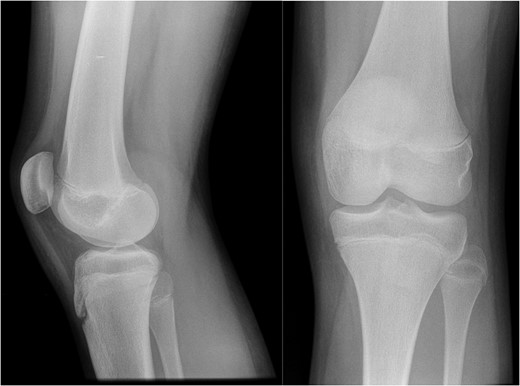

AP and lateral radiographs of the knee from the time of initial injury.